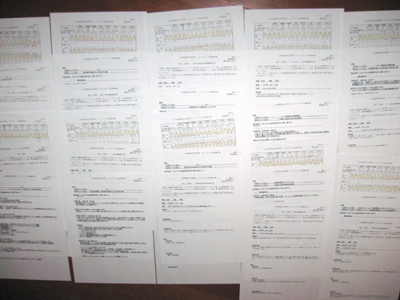

'08 9主治医の紹介で当院に来院されて以来、さすがに熱心にプラークコントロールに取り組んでいただきました。'08 9~'10 2のプロービングデプスの変化です。青は6mm以上、赤はBOPを示しています。

当院で歯周治療ののちメインテナンス10年以上継続している患者さんのなかで「初診時の状態ワースト10」の資料を集めてみました。

これら全て初診時のプラークスコア80%以上、プロービングデプス7mm以上が50~60%、4mm以上なら80%をゆうに超える重症例ばかりです。最年少は初診時37歳(これは侵襲性歯周炎もしくは急速進行性若年性歯周炎でしょう),その後18年のメンテナンス,というケースをはじめ、皆、私の歯科医としての想いを込めて治療、メインテナンスを続けてきた重症例ばかりですから細かい数字はともかく患者さんのプロフィールや治療経過、口腔内の状態等は空でいえます。当然、初診時は悪くても全て現在は良好な経過をたどっています。

資料を全てインプットするというひどく単調で煩わしい仕事を終えてあらためて眺めてみていたら、、、10症例の平均年齢は「47歳(!)」なのです。記憶に残るほどの重症例の初診時年齢が想いの外に低く、これは驚きでした。ついつい自分の年齢と比べてしまうのかもしれませんが、まれに見る重症例の歯周病はすでにこの年齢までには進みきっている、ということなのでしょうか。あるいは比較的若くして重症であることが重症たる所以なのかもしれません。

これらの詳細についてよくよくみれば何らかの形でひとかたりできるかもしれません。